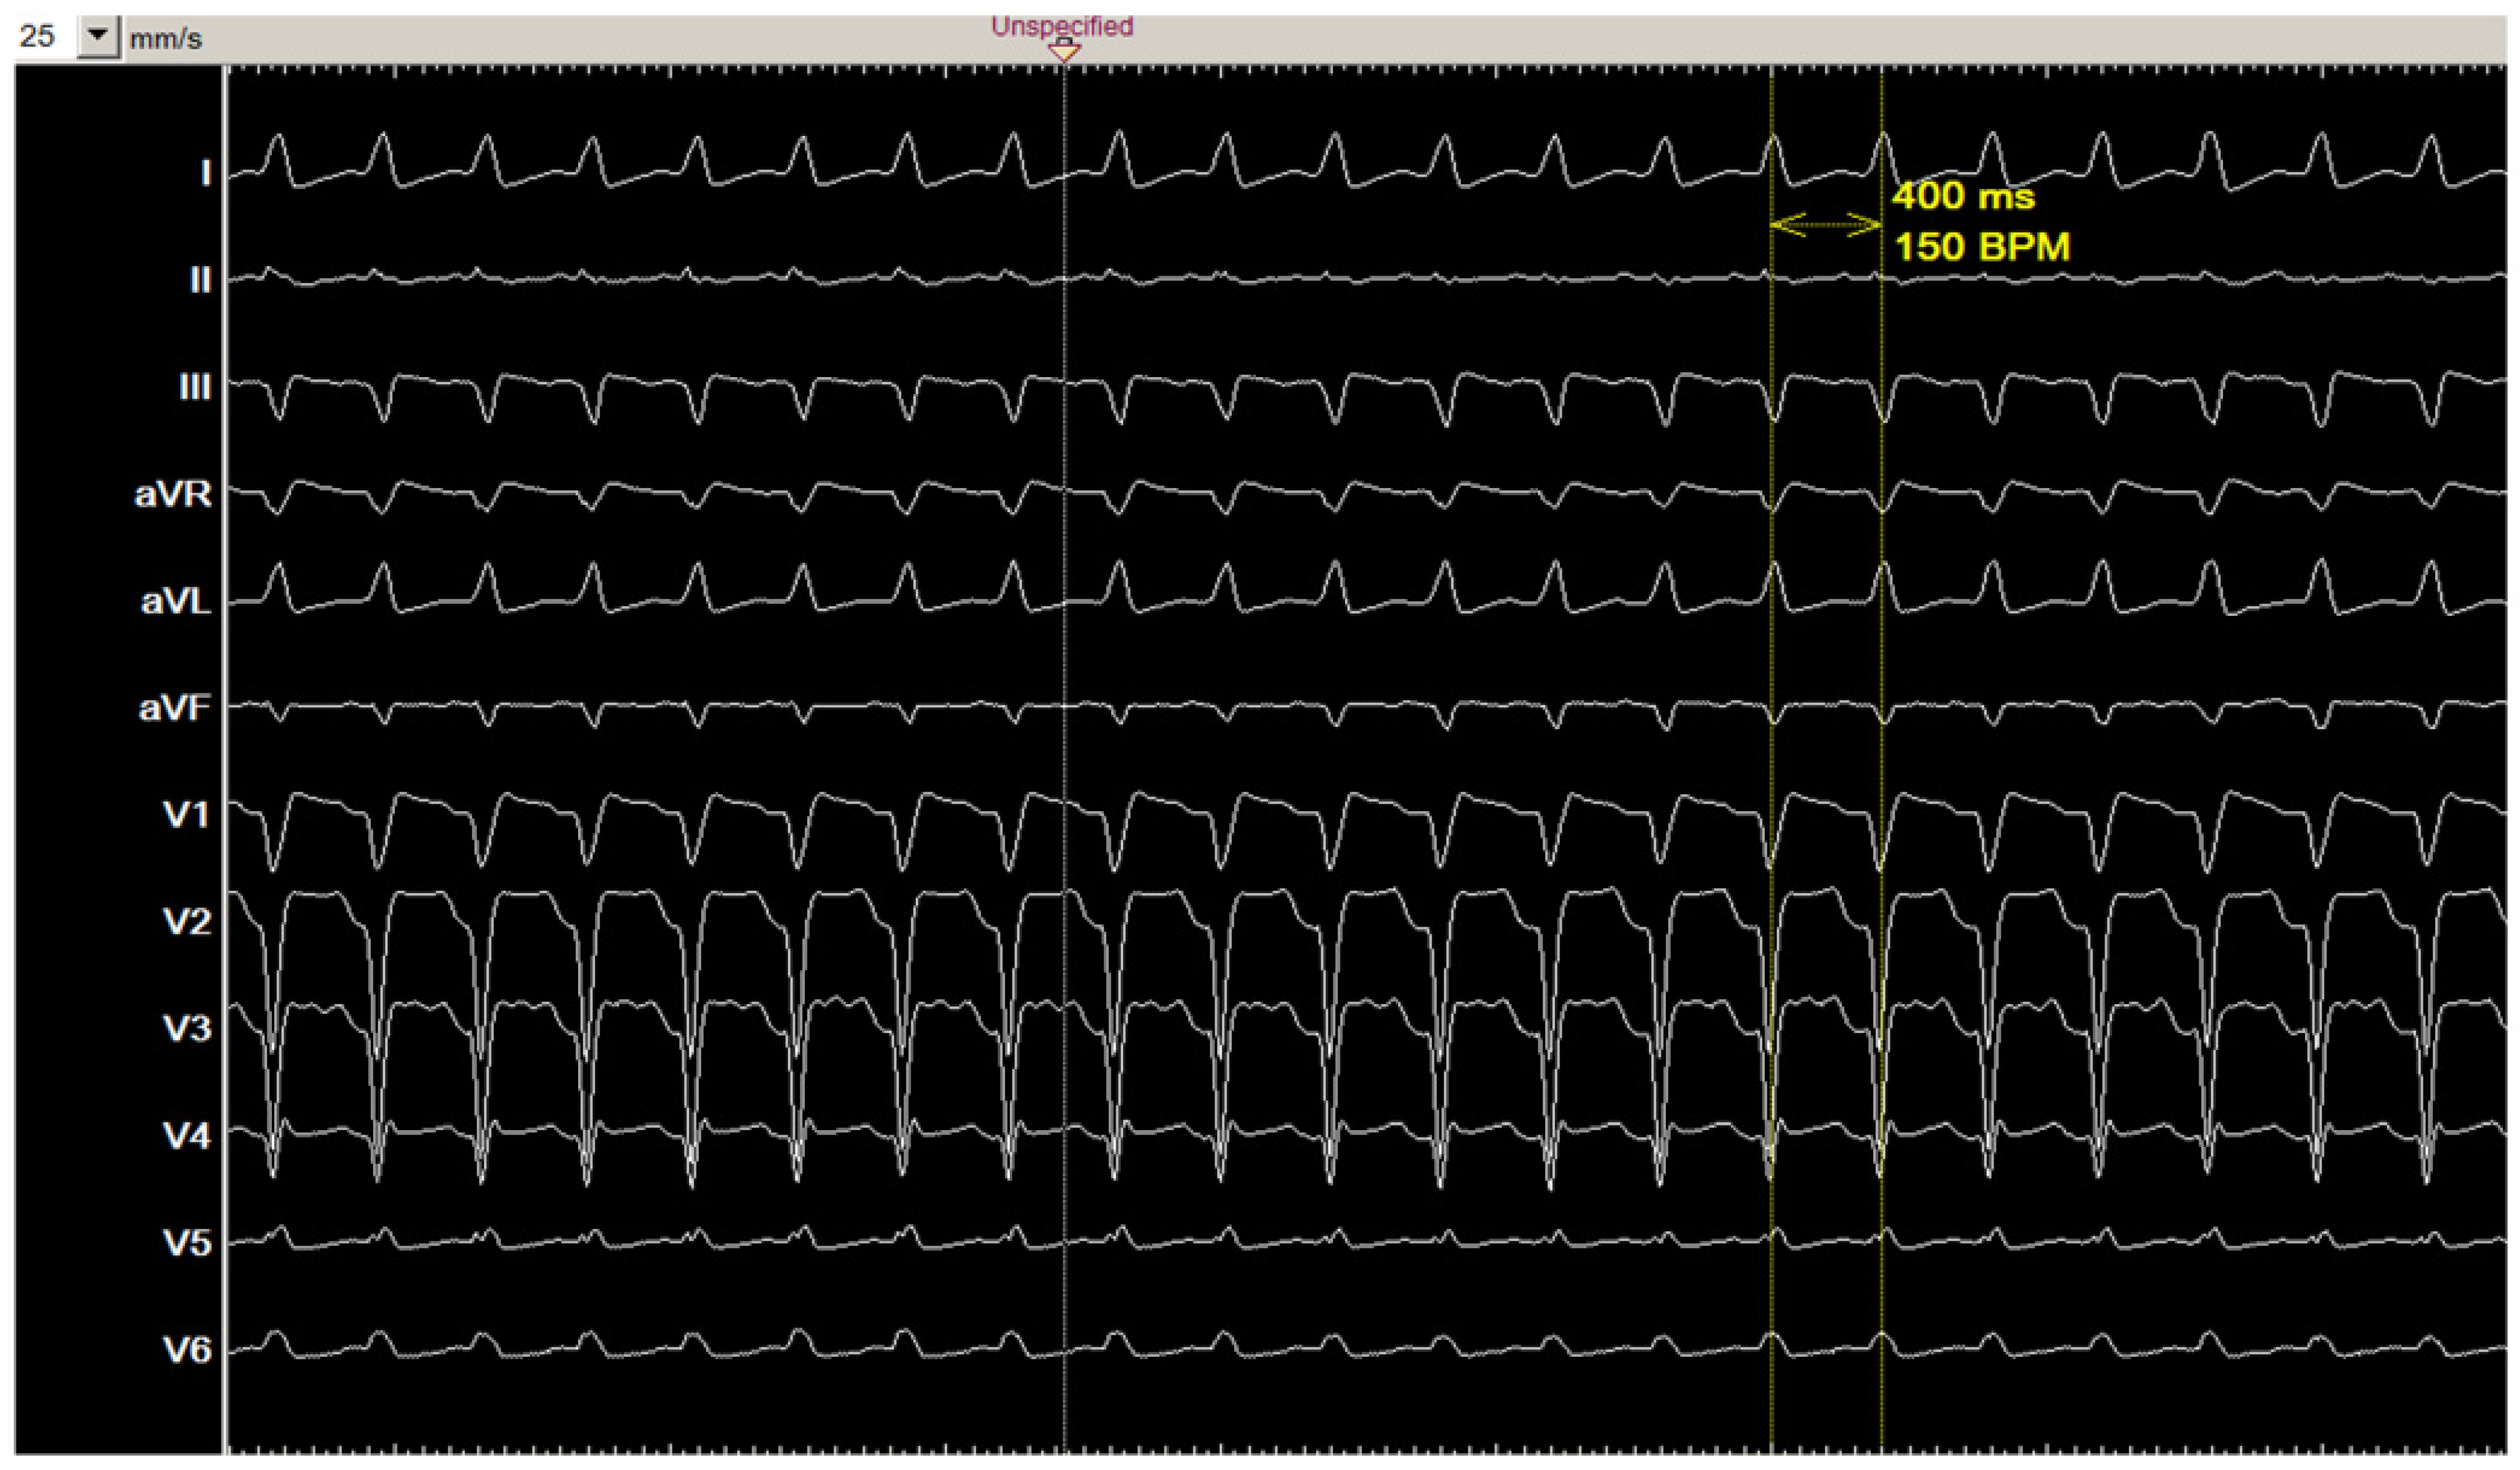

2.1. Clinical Presentation

2.2. Diagnostic Workup